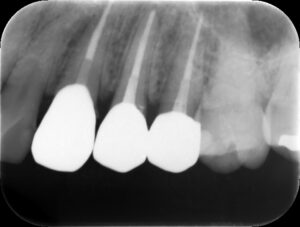

根管充填後レントゲン。歯の痛みや歯茎の腫れが改善したため、バイオセラミックシーラーおよびガッタパーチャにて根管充填を行った。根管治療は2回、2週間で終了。

治療後レントゲン。適切な補綴(被せ物)により治療を終了。的確な診断および治療を行うことで、長年の悩みから解放された。我々は、無暗に患者さんの大切な人生の時間を奪ってはいけない。